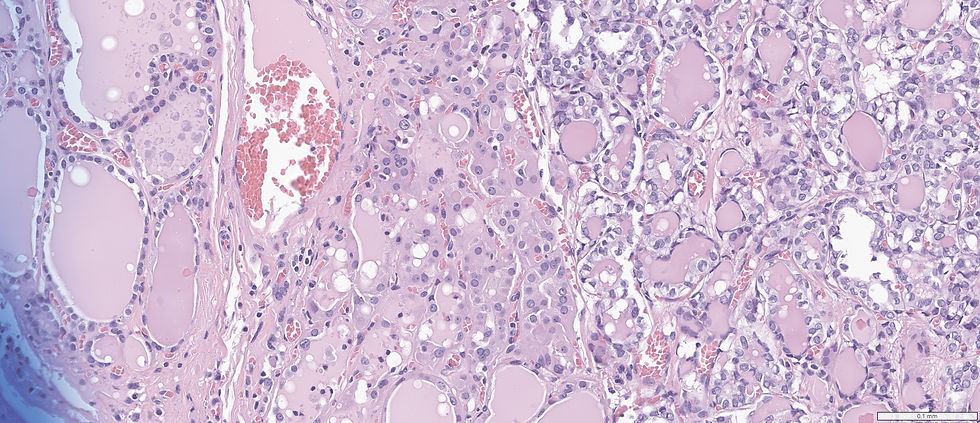

A 45-year-old female presented with a 4.0 cm mass in the left thyroid.

Is this papillary thyroid carcinoma or benign neoplasm?

This is minimally invasive follicular variant of PTC. However the nuclei features are subtle. See the table below: